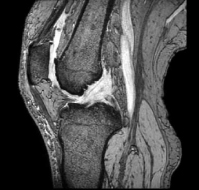

MRI検査

整形外科領域